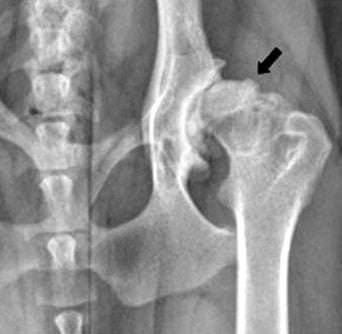

RADIOGRAFÍAS: Las radiografías son esenciales para confirmar el diagnóstico y evaluar la gravedad de la displasia. Estas imágenes permiten observar cómo encajan las estructuras óseas en la articulación.